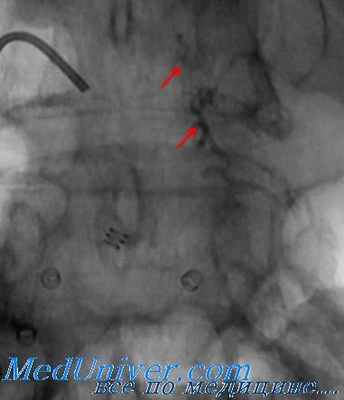

Ангиография проводится сразу после катетеризации артериального сосуда. Как правило, первой должна быть выполнена «струйная» аортография. При выявлении ранений крупных кровеносных сосудов таза специалист по ангиографии должен определить, какой именно сосуд поврежден. Следует помнить о возможности ретроперитонеального кровотечения в отдаленной от таза локализации. Наиболее типичным примером является комбинированный перелом таза и поясничного отдела позвоночника. При этом кровотечение бывает обусловлено повреждением поясничной артерии, что часто выявляется при проведении ангиографического исследования.

Если при аортографии повреждение артериального сосуда не установлено, следует продолжить исследование методом селективной ангиографии. Механизм травмы и модель перелома позволяют предположить повреждение внутренней подвздошной артерии, и изображение именно этого сосуда должно быть получено в первую очередь. Прежде, чем завершить исследование, следует получить изображение всего сосудистого русла таза по причине возможного обнаружения нескольких источников кровотечения. По некоторым данным, в 57% выявленных повреждений сосудов, имели место кровотечения разной локализации.

В идеале, для эмболизации желательно выбрать наиболее подходящий артериальный сосуд. Если при селективной ангиографии достигнуто место кровотечения, то для эмболизации часто выбирают гемостатический гель (Gelfoam). Каждый кусочек Gelfoam поочередно погружается в шприц и вводится под контролем рентгеноскопии. Гель действует на протяжении нескольких недель, а затем растворяется, при этом кровотечение не возобновляется. При большом диаметре кровоточащего артериального сосуда используют спирали, изготовленные из нержавеющей стали. Вызываемая ими окклюзия бывает иногда недостаточной, тогда ее можно дополнить введением гемостатической губки.

Эмболизация при помощи спиралей впервые описана Sclafani et al, которые предложили использовать ее для предупреждения осложнений, вызванных попаданием гелеоб-разного гемостатического вещества в капиллярное русло. По опубликованным материалам, такими осложнениями могут явиться трофические нарушения кожных покровов, парез нижних конечностей, мионекроз и половое бессилие. Техника эмболизации включает введение микроспиралей через специальные коаксиальные катетеры в неповрежденные сосуды, расположенные дистальнее места повреждения. Затем гемостатической губкой проводится эмболизация того участка артерии, который расположен выше места повреждения. Микроспирали защищают капиллярный кровоток от окклюзии гелем. После завершения эмболизации проводится ангиографический контроль коллатерального кровообращения. Техника позволяет выключить из кровообращения поврежденные сосуды, и обеспечивает окклюзию только поврежденного участка артерии.

Последний технический момент эмболизации касается сосудов с окклюзией на ангиограмме. Вероятнее всего, так выглядят поврежденные сосуды, кровотечение из которых самостоятельно прекратилось еще до проведения ангиографии. Поскольку иногда возникает искушение игнорировать такие сосуды, авторы рекомендуют соблюдать осторожность, ведь каждый хирург, заметивший во время операции затромбированную артерию, обязательно наложит на нее лигатуру, чтобы не допустить отсроченного кровотечения. К тому же, некоторые повреждения сосудов вызывают спазм артерии, что при диагностическом исследовании выглядит как окклюзия. Тогда, после разрешения спазма, кровотечение возобновляется. При наличии технической возможности, целесообразно выполнить эмболиза-цию подобных сосудов.